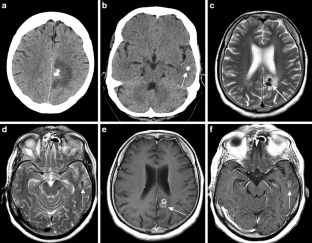

The CNS TB can be manifested (1) diffuse as tuberculous meningitis (TBM), (2) localized as tuberculoma or (3) tuberculous abscess or (4) in extradural and intradural spinal infections. Information on clinical presentation, underlying pathology and the distinguishing features is demonstrated. The TBM is further described, which may lead to cranial nerve palsy, hydrocephalus and infarction due to associated arteritis of the basal perforators. The differential diagnoses are vast and include other infections, such as bacterial, viral or fungal meningoencephalitis, malignant causes or systemic inflammation with CNS. Complicating factors of diagnosis and treatment are HIV coinfection, multi-drug resistance and TB-associated immune reconstitution inflammatory syndrome (IRIS).